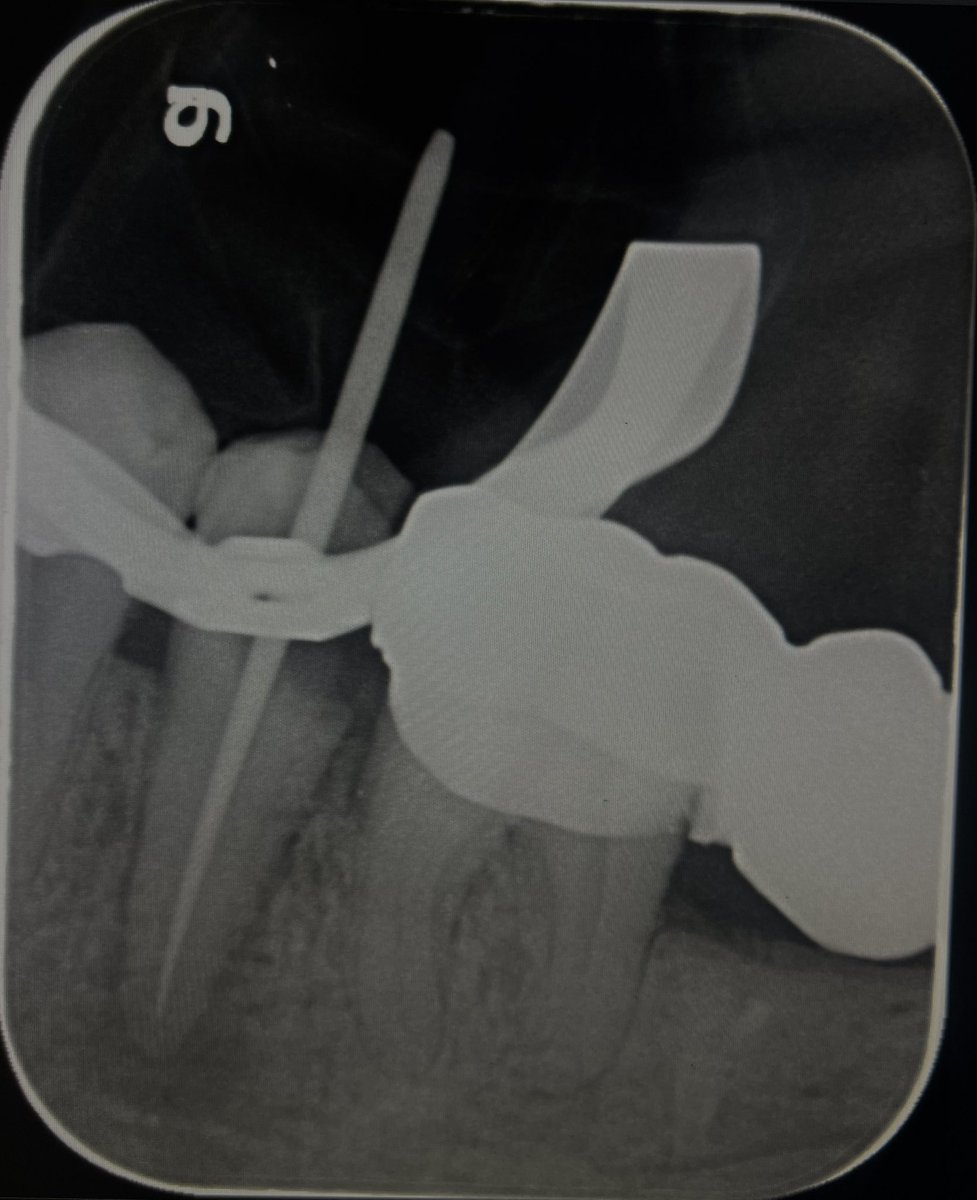

حالة جميلة لصباح اليوم 🙏🏻

Root Canal Treatment #34

Dx:SIP+SAP

Gingival overgrowth and deep caries in the distal wall, Rebuild the distal wall to achieve optimum isolation ✨

Next Step: Crown